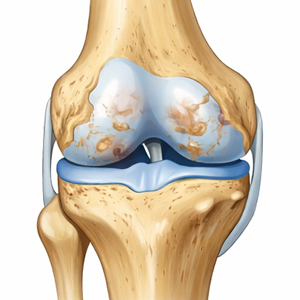

Stadium III

Fortgeschritten

Lücken im Knorpel

Stadium IV

Schwere Arthrose

60% des Knorpels verloren